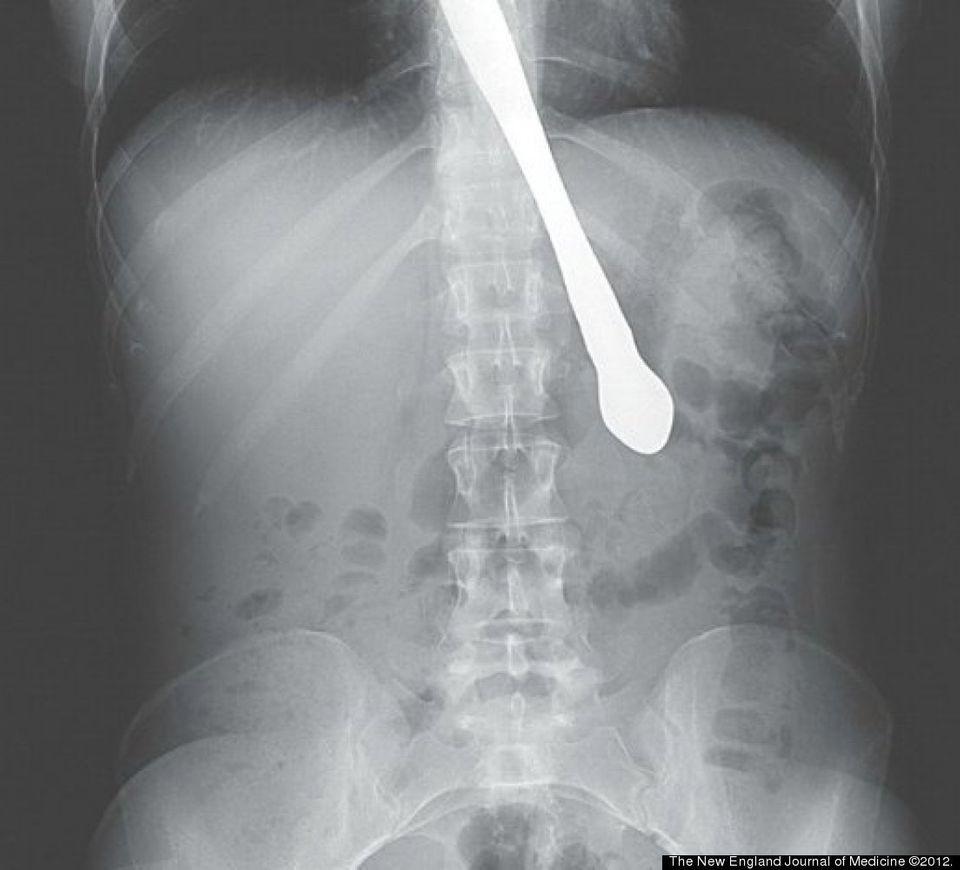

Lee Gardner đã nuốt 1 chiếc dĩa nhựa vào bụng và 10 năm sau nó mới được lấy ra sau 1 ca phẫu thuật.